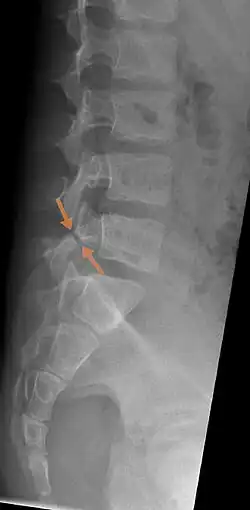

Arrows show break in pars interarticularis at L5. X-Ray of lumbar spine, lateral projection, in an 11-year-old boy | |

The scottie dog sign It was once used as a diagnostic sign in x-rays, for lumbar spondylolysis, but it is not commonly in use nowadays because of the advent of more sensitive diagnostic methods such as the CT scan and MRI scan. If spondylolysis is present, the pars interarticularis, or the neck of the dog, gives the appearance of a Scottish Terrier with a collar around its neck.[7]

X-Ray

X-rays (electromagnetic radiation) are projected through the body to produce an image of its internal structures. The radiation is more attenuated (absorbed) by the denser tissues of the body (i.e. bone) than the softer tissues (i.e. muscles, organs, etc.) creating a picture composed of shades of grey ranging from white to black. A vertebra with a fracture or defect of the pars interarticularis will have a dark mark through this region of bone. Since this is difficult to see on the AP (anterior posterior) x-ray view an oblique x-ray of the lumbar spine can usually identify the spondylolysis. If inconclusive a further CT scan can produce a 3-dimensional images to more clearly show the defect although the exam increases the patients radiation dose by at least an order of magnitude than plain x-rays.[16][17]